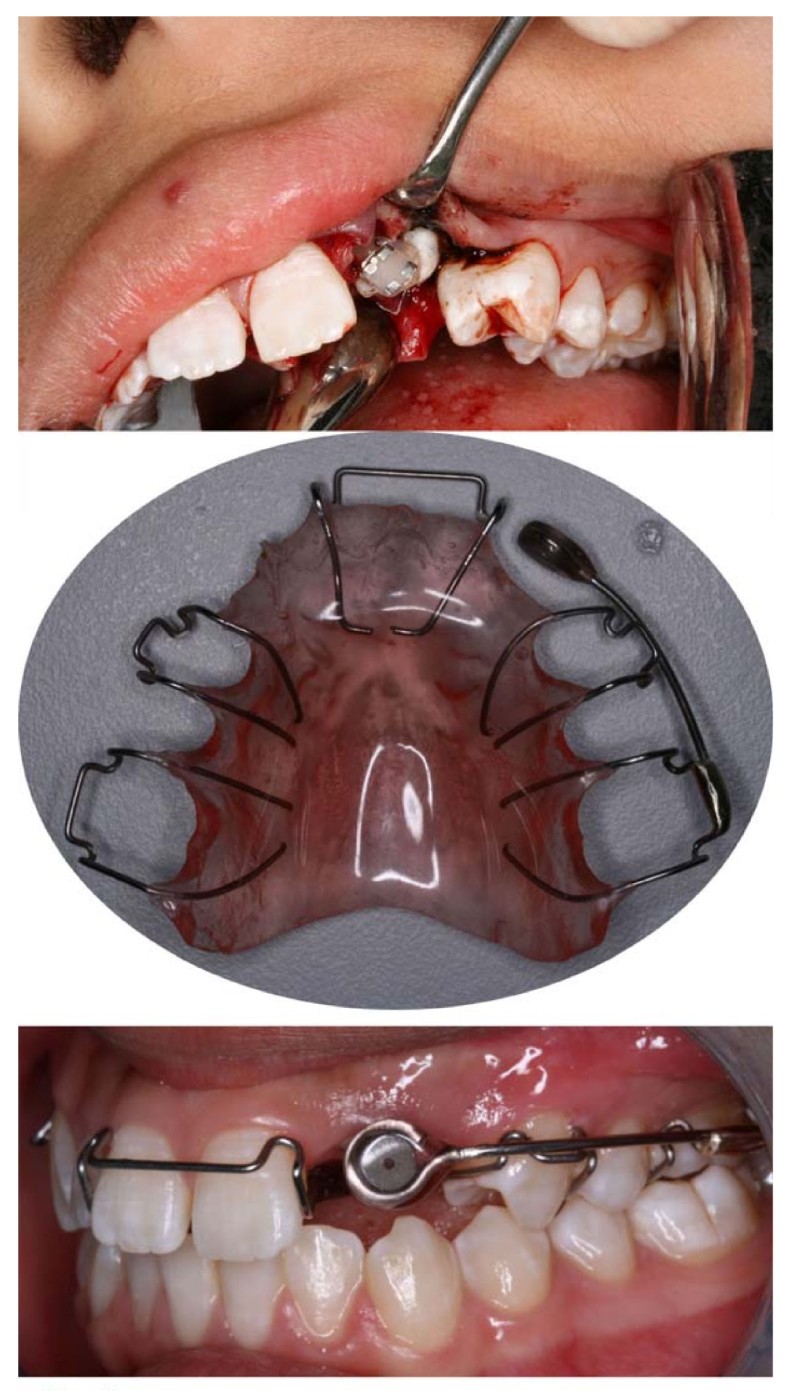

Figure 1 from A case series of orthodontic traction of maxillary Orthodontic Traction Orthodontic brackets are placed before the surgical exposure. Teeth are required to be aligned and leveled because orthodontic. It illustrates the topic by presenting a treatment delivered to a 13 year 7 months old. A ramus miniscrew is an effective and viable treatment option for the orthodontic traction of deeply impacted mandibular molars. Thus, this work aims to show,. Transalveolar. Orthodontic Traction.

Surgical exposure and orthodontic traction with a removable Orthodontic Traction A ramus miniscrew is an effective and viable treatment option for the orthodontic traction of deeply impacted mandibular molars. Transalveolar autotransplantation (9 canines) and orthodontic traction (8 canines) were the most frequently chosen treatment methods. The principles of orthodontic mechanics strongly influence the success of impacted canine traction. Orthodontic brackets are placed before the surgical exposure. Teeth are required to. Orthodontic Traction.